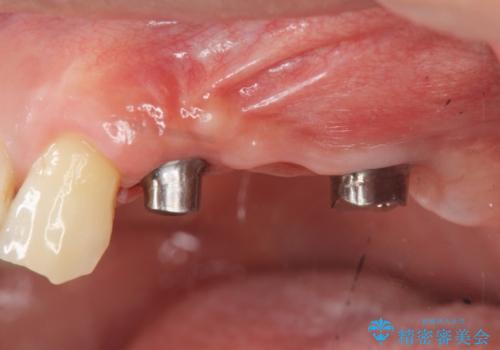

- 重度の虫歯により左上の歯を失い、インプラント治療は怖いため嫌厭して放置していたが、いよいよ食事に困りしっかりと噛めるようになりたいと希望され来院されました。

残存している小臼歯も虫歯が大きく保存が難しいため抜去を行い造骨を含めたインプラント治療を行います。

しっかりと造骨を行ったことでインプラント周囲には十分な量の骨が存在し安定したインプラント周囲環境を整えることができました。